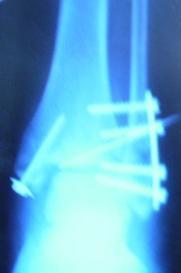

вчера была на МРЭК. По настоянию юриста, повторно. С целью получить письменные трудовые рекомендации (1) и заключение о % потери профессиональной трудоспособности (2).

1. Получила заключение: я со своей такой ножкой могу работать где угодно и кем угодно. Практически абсолютно здорова. Фигня, что я не могу быстро и много ходить, бегать, прыгать, водить автомобиль и подниматься на носочки. Фигня заключение травсматолога, что у меня посттравматический артроз и контрактура и что я нуждаюсь в рациональном трудоустройстве.